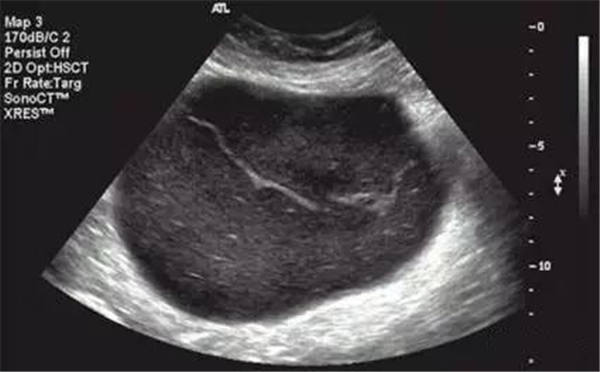

2、宮腔積血、積膿、積液

(宮腔積液)